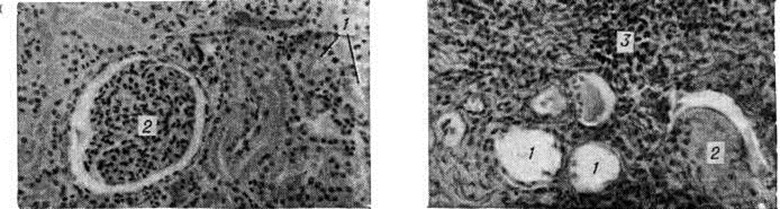

Рисунок 2.

Микроскопическая картина здоровой почки (слева) и почки при гидронефрозе (справа): просвет канальцев (1) резко расширен, клубочек (2) склерозирован; выражено разрастание соединительной ткани, инфильтрированной круглоклеточными элементами (5).

Патологическая анатомия. Морфологически изменения при Гидронефроз зависят в первую очередь от стадии болезни. В начальных стадиях почка (независимо от внутри- или внепочечной локализации лоханки) мало отличается от здоровой. В основном патологический изменения выражены в чашечках и лоханке. Под действием повышенного внутрилоханочного давления увеличивается ёмкость чашечек и в значительной степени изменяется их конфигурация — они становятся круглыми, шейка их укорачивается и увеличивается в поперечном размере. Подобная картина чаще наблюдается при внутрипочечном расположении лоханки; она носит название гидрокаликоз (расширение одной или нескольких чашечек). Одновременно с увеличением размеров чашечек нарастает ёмкость лоханки; это происходит быстрее при внепочечном её расположении. Таким образом, к гидрокаликозу присоединяется и пиелоэктазия, а при низких локализациях препятствий развивается гидроуретеронефроз. Стенка лоханки постепенно истончается вследствие прогрессирующей атрофии гладких мышечных волокон и замены их соединительной тканью; погибают нервные окончания; облитерируются кровеносные и лимфатические, сосуды лоханки. Существует параллелизм между длительностью существования препятствия оттоку мочи и степенью нарушения нервно-мышечного тонуса лоханки. В терминальной стадии Гидронефроз лоханка представляет дряблый тонкостенный мешок, стенки которого в основном состоят из грубоволокнистой соединительной ткани. Прогрессивно растягивающаяся лоханка оттесняет почечную паренхиму к периферии, сдавливает форникальные вены и артериолы. В почечной паренхиме постепенно развиваются явления атрофии и склероза (рисунок 2), позже почка превращается в соединительнотканный мешок с отдельными остатками нормальной ткани. Наблюдаются и различные изменения сосудов почки — артерии становятся извитыми, удлинёнными, расширенными. Артериография удалённых почек и прижизненная серийная ангиография позволили обнаружить сужения магистральной почечной артерии, облитерацию и запустевание её ветвей. При этом, чем глубже выражена атрофия почки, тем уже их просвет, тем дальше отстоят ветви одна от другой (Н. A. Лoпаткин, 1961). В этой стадии Гидронефроз почка бывает резко увеличена в размерах, корковый слой её очень тонкий (цветной рисунок 1 и 2).